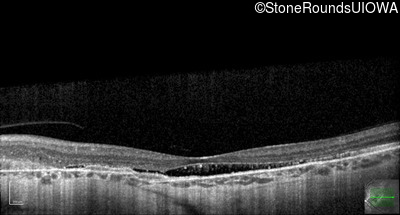

Optical Coherence Tomography - Left - 20/160

Exemplar / OCT Stack

OCT Stack